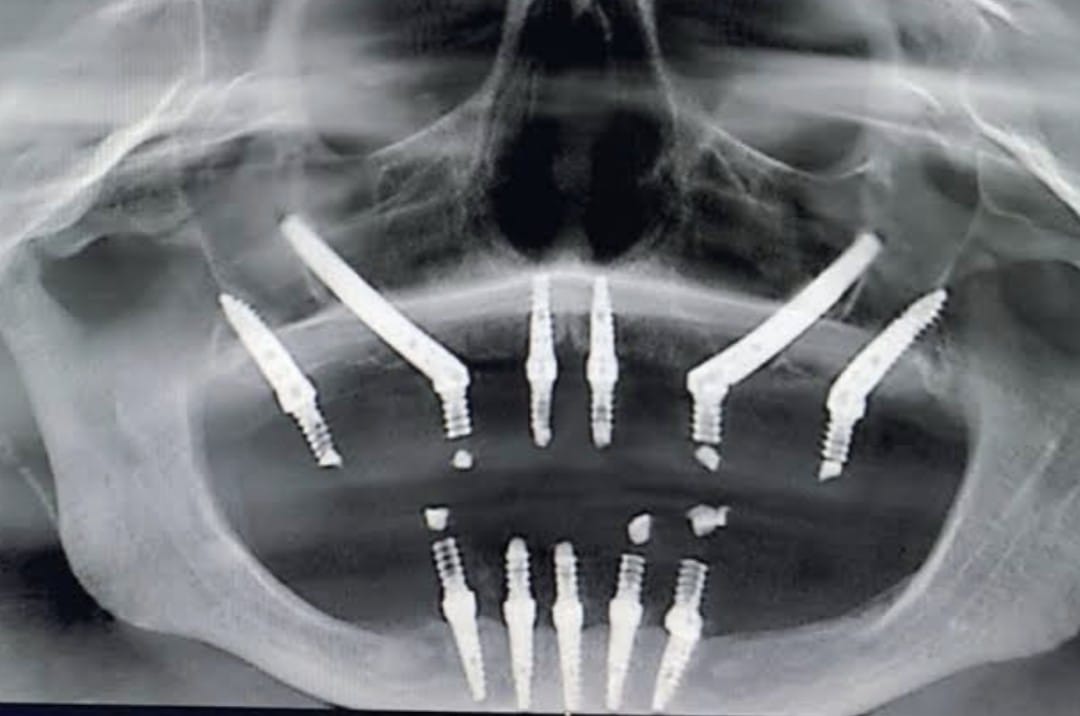

Dental implants are a modern and reliable solution for replacing missing teeth. They are designed to restore both the appearance and function of natural teeth. A dental implant consists of a small titanium post that is surgically placed into the jawbone, where it acts as an artificial root for the missing tooth. This procedure helps provide a stable and long-lasting foundation for the replacement tooth.

Dental implants are commonly recommended for patients who have lost one or more teeth due to injury, decay, or gum disease. Once the implant is placed into the jawbone, it gradually integrates with the bone through a natural healing process, providing strong support for the artificial tooth. After the healing period, a dental crown is attached to the implant to restore the appearance and function of the natural tooth. One of the major advantages of dental implants is that they help preserve the jawbone and prevent bone loss that can occur after tooth loss. Unlike removable dentures, implants are fixed in place and function similarly to natural teeth, allowing patients to chew, speak, and smile with confidence. With proper oral hygiene and regular dental check-ups, dental implants can last for many years. This treatment provides a durable and effective solution for restoring missing teeth and improving overall oral health and facial aesthetics.